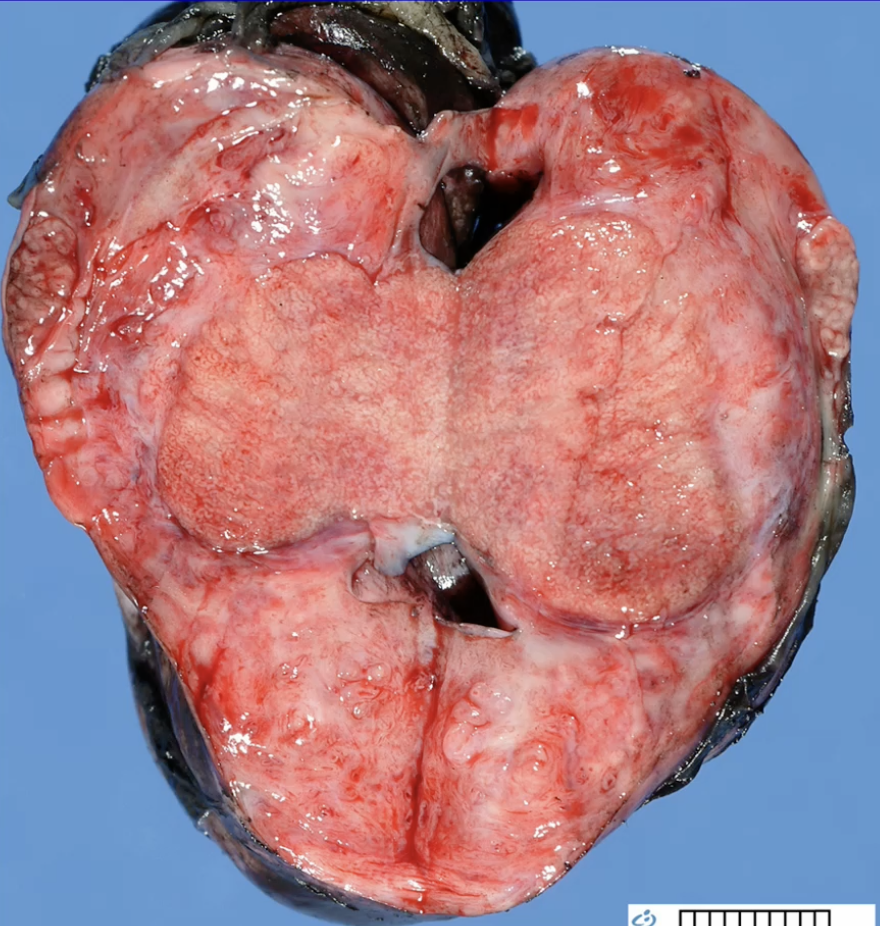

Seminoma - 30-40 yo men and good prognosis

Seminoma

PLAP stain Seminoma